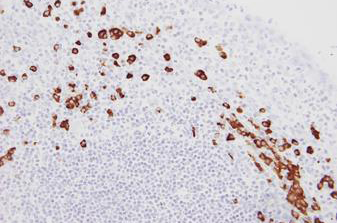

Human tonsil: in situ hybridization for kappa mRNA using Kappa Probe, Anti-Fluorescein Antibody and BOND Polymer Refine Detection.

Kappa Probe is used for the qualitative identification of Kappa light chain messenger RNA (mRNA) in formalin-fixed, paraffin-embedded tissue by in situ hybridization (ISH) using the automated BOND system.

There are five classes of immunoglobulin, determined by the type of heavy chain. In contrast, there are only two types of light chain: Kappa or Lambda. Each individual immunogloblin molecule is composed of one of five classes of heavy chains and either Kappa or Lambda light chains. In normal human lymphoid populations, the ratio of Kappa to Lambda light chains is approximately 2:1.

Kappa Probe is used in conjunction with Lambda Probe for the detection of antibody producing B-cells in formalin-fixed, paraffin embedded tissue.